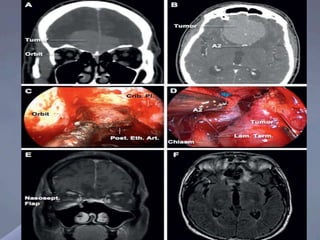

Large olfactory groove meningioma. (A) Preoperative

(coronal)

(B) Axial section close relation of tumor to anterior cerebral arteries at the

proximal A2 segment.

(C) Intraoperative- The right lamina papyracea removed to expose the

periorbita and provide access to the orbital roof. The anterior and posterior

ethmoidal arteries coagulated and sectioned to expose the anterior skull base

and provide early devascularization of the tumor.

(D) Intraoperative- Once the tumor has been extensively debulked, gentle

extracapsular dissection is performed.

(E) Postoperative-T1-weighted MRI (coronal section) complete resection

of the tumor, cribriform plate, and crista galli. The anterior skull

base reconstructed with the nasoseptal flap.

(F) Postoperative FLAIR sequence MRI (axial section) showing nearly complete

resolution of the signal changes and minimal encephalomalacia.